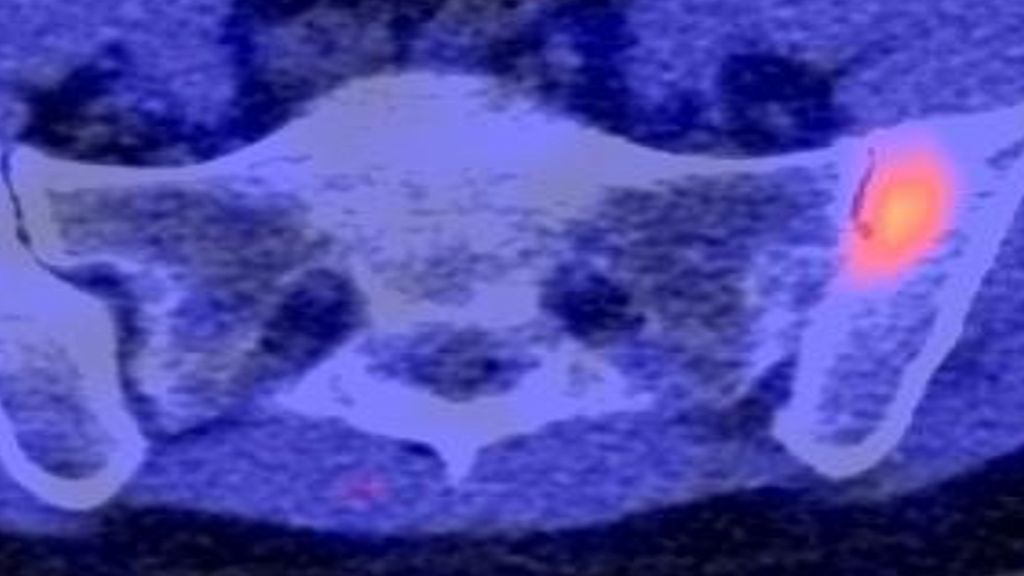

Inwieweit diese präklinischen Befunde auf den Menschen übertragbar sind, untersuchten Ramming und seine Mitarbeiter in einer rezenten Arbeit.5 In die Studie wurden 20 Patienten mit rheumatoider Arthritis (RA), 50 Patienten mit Psoriasisarthritis (PsA) und 50 Patienten mit axialer Spondyloarthritis (SpA) eingeschlossen. Zunächst wurden mittels FAPI-PET-CT Gewebereaktionen in verschiedenen anatomischen Regionen visualisiert (Hüftgelenksynovitis, Sakroiliitis, Tendinitis, Ellenbogenenthesitis, Facettengelenkassoziationen, Daktylitis). Bemerkenswert ist, dass die Intensität der FAPI-PET-CT-Signale mit den jeweiligen klinischen Scores (DAPSA bei PsA, SPARCC bei Enthesitis, DAS28 bei RA und PsA, ASDAS und BASDAI bei SpA) korrelierte.

In einem nächsten Schritt wurden die Probanden einer FAPI-PET-CT sowie einer MRT unterzogen. Die im MRT detektierten Läsionen wurden systematisch kategorisiert in 1. erosive Schädigungen, 2. osteoproliferative Schädigung bzw. 3. Entzündung ohne Hinweis auf eine Schädigung. Und tatsächlich zeigte sich, dass die im MRT detektierten Gelenksschädigungen mit einer erhöhten FAPI-PET-Signalintensität assoziiert waren, während Läsionen, die lediglich eine Inflammation ohne Gelenksschaden zeigten, kein FAPI-PET-Signal lieferten.

Untersucht wurden übrigens auch die Effekte einer Biologikatherapie auf die Gewebereaktion. Dabei zeigte sich, dass sowohl TNF-α-Inhibitoren als auch IL-17A-Blocker die mesenchymale Aktivität reduzierten – und zwar relativ rasch. So war bei einem beispielhaft gezeigten Patienten mit einer Sakroiliitis bereits nach 3 Monaten unter IL-17A-Inhibitor-Therapie das mesenchymale Signal komplett verschwunden.